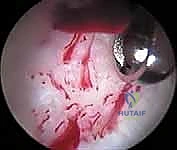

4. الإجراء العلاجي (The Intervention)

بناءً على ما تم تشخيصه، يقوم الجراح بتنفيذ الإجراءات التالية باستخدام أدوات آلية دقيقة (Shavers, Burrs, Radiofrequency probes):

* إصلاح الشفا الحقي (Labral Repair): إذا كان الشفا ممزقاً ولكن نسيجه لا يزال جيداً، يتم إعادة تثبيته في حافة الحُق باستخدام خطاطيف صغيرة جداً (Suture Anchors) تزرع في العظم وتمرر خيوطاً قوية لربط النسيج الممزق.

* تنظيف الشفا (Labral Debridement): إذا كان النسيج الممزق تالفاً جداً ولا يمكن خياطته، يتم تشذيبه وإزالة الأجزاء المتهتكة لتخفيف الألم ومن